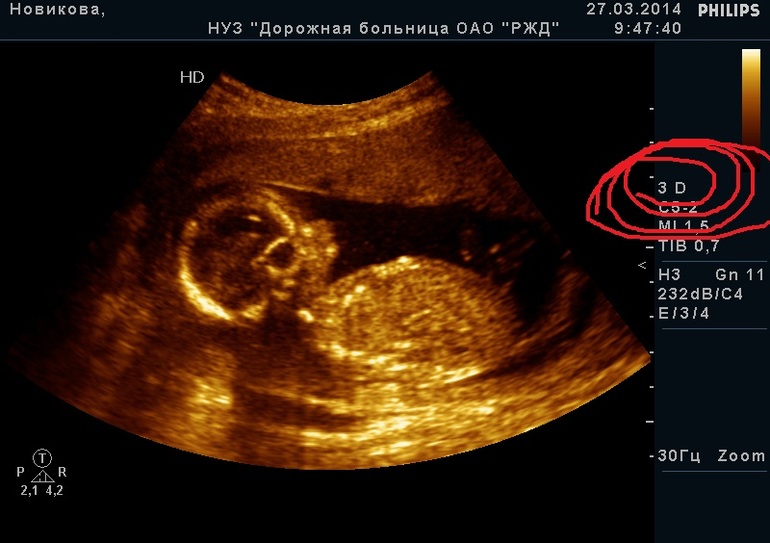

Почему нет???Я полтара года назад все 3 УЗИ 3Д делала в ЖД больнице в Красноярске,цветные фото и видио на диске на руки дали

это не 3д.... мы тож такое делали. обычное 2д только желто-оранжевое...сравните с 3д хотя бы отсюда и все поймете. .. сама удивлена, что так

Капец но пишут они почему то,что 3д,и в прайсе тоже пишут цену за 3д и за обычное УЗИ отдельно

Ну я сравнила зд УЗИ с интернета и моё,ничем оно не отличается,такое же оранжевое фото

цветное, но не объемное

688e33bedfe125456fb232a5be533716.jpg 994cebd4243392bbc9f021639d9d7e6b.jpg первое из жд, второе нормальное 3д